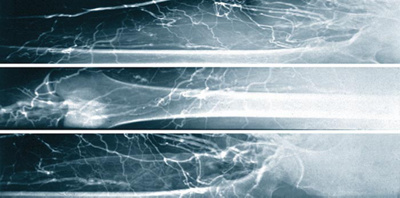

Abb. 2

4-Etagen-Thrombose: Alle Venen am Unter- und Oberschenkel sowie im Becken sind mit frischen Thromben aufgefüllt.

Abb. 3

Nach der Kombinationstherapie: Alle Venen sind frei von Thromben und die Venenklappen sind intakt geblieben.